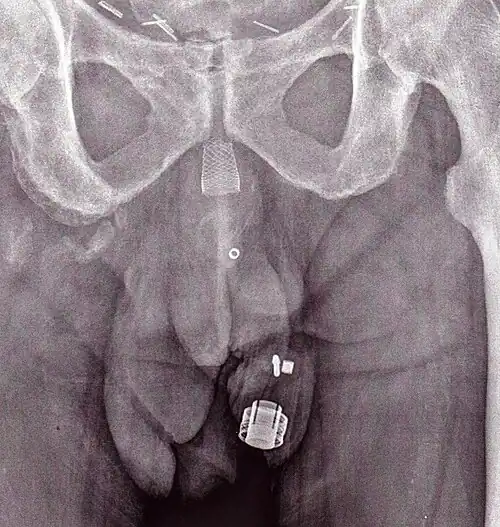

CT scan (coronal reconstruction) showing an AMS 800 in a woman -